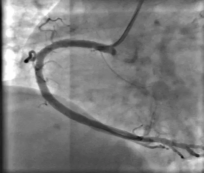

当天开展的两台手术中:病例1为36岁男性患者,因反复胸痛3年,再发20天来院求诊,经完善心电图等相关检查,予以行冠状动脉造影,排除冠心病、心绞痛致病可能。病例2为 60岁女性患者,既往有冠心病支架植入术病史,此次因胸痛不适来院治疗。经行冠状动脉造影,发现其右侧冠状动脉近中段有一处89.9%的血管狭窄,术中在征得患者及家属同意后,立即予以行冠状动脉支架植入术。术后患者生命体征平稳,截止目前未再复发胸痛。

支架植入术前 术后